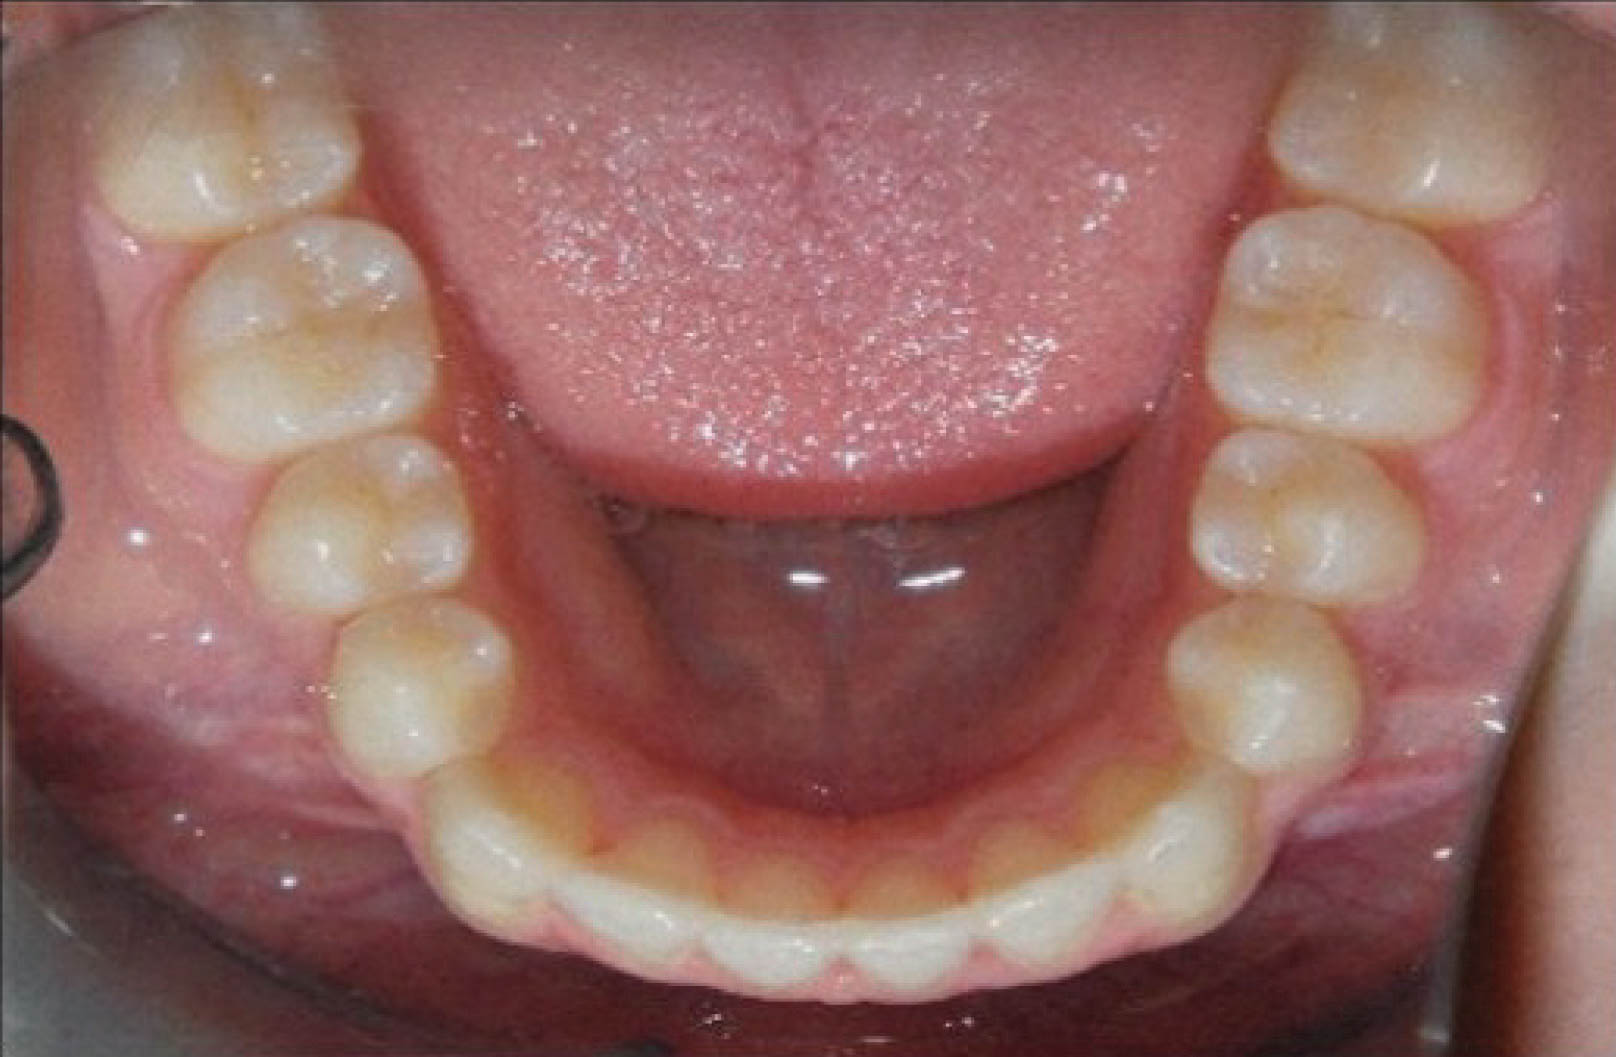

شکل 145-6 نحوه مرتب شدن دندانهای قدام پایین با 0.3mm استریپ هر کنتاکت را نشان میدهد. در پایان درمان قوس پایین کاملاً صاف شده است (شکل 146-6).

شکل 145-6